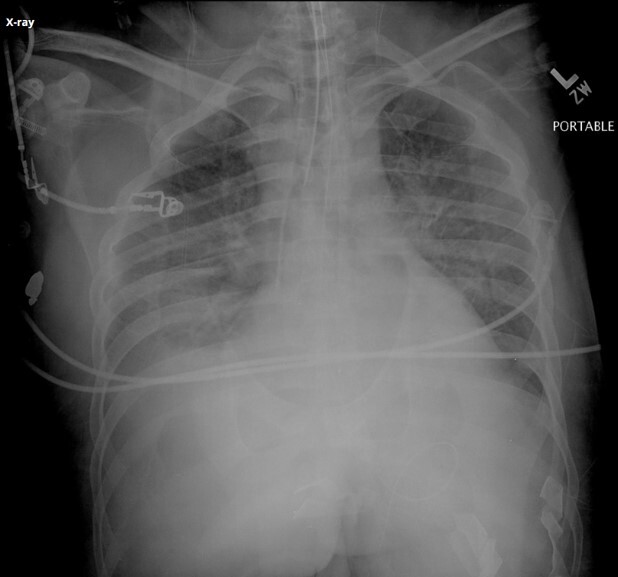

11

Q

What is the cause of the artifact (red circle) seen

in the attached image?

A

Back scatter from high technique and reduced shielding on back of detector